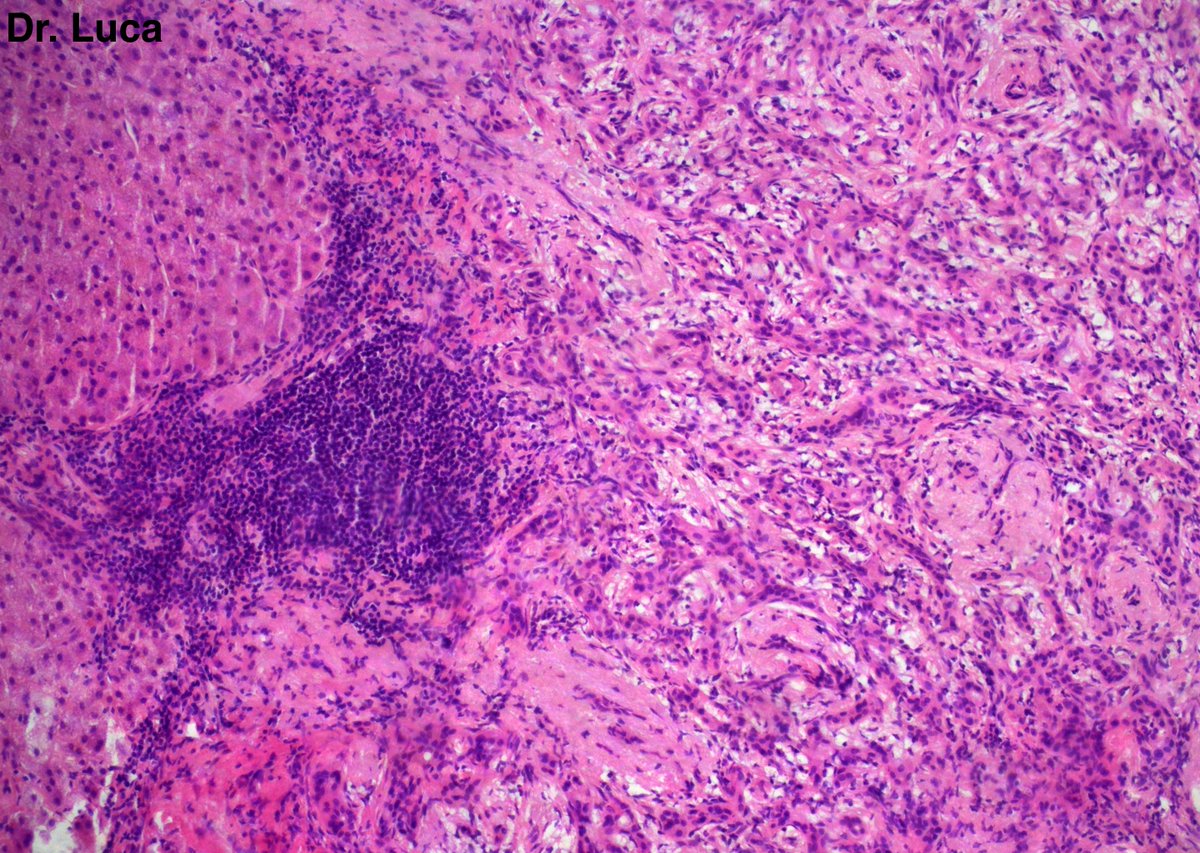

@Pathmath1 @SumantaDas_7 @PoloniaAntonio @ivanaspath @AnapathResident @bansar7 @goziemnweke @Teclis82 @Dr_Brian_Cox @DrBMcGinn @ariella8 @nusrat_xahra @DrRusella_Mirza @glinglerimek @kis_lorand @Venkateshgilly2 @DrBonita16 @DrPayelMondal @DrGeeONE @anjuthevirgo @niki_2389 @pepeheffernan @AngeloCassisa @NeoCrazee @TristanRutland7 Yes, it's a cancer with PNI...I show you the "superficial" layer of this cancer...what is the cancer? and what is the organ? #Pathology #GIpath #PathTwitter #PathResidents #pathboards

2

11